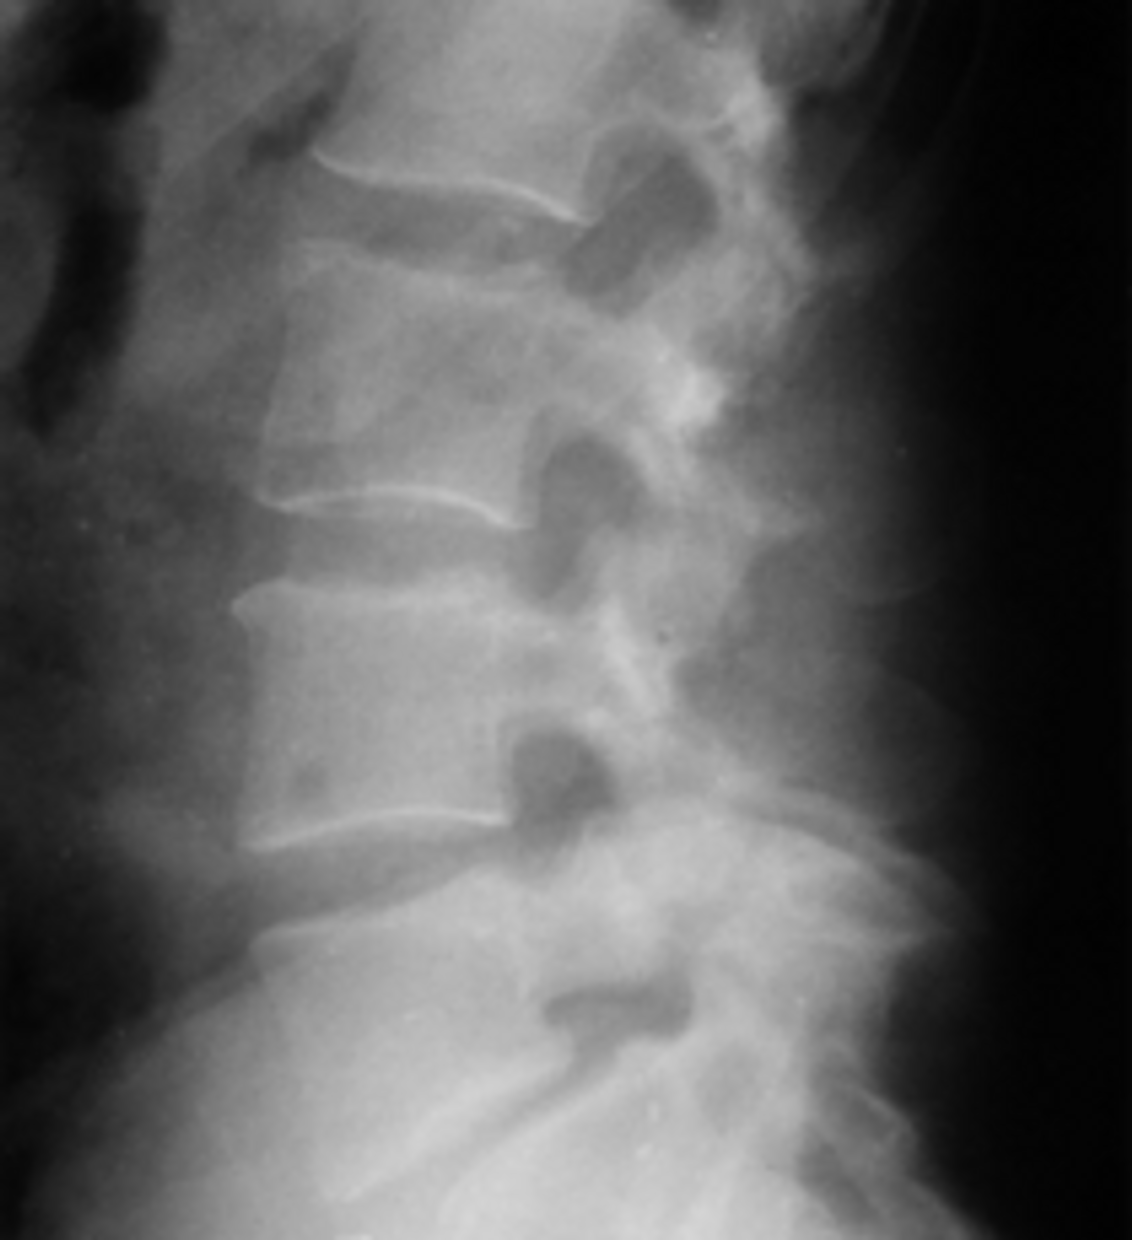

This condition is usually found in patients over 50 years of age. The pelvis is a common location for the disorder. Thickening of the pelvic brim, accentuation of the trabecular pattern, sclerosis and protrusio acetabul are common features. This is an example of a sclerotic form. Other common locations of this condition are the skull, vertebrae and long bones. Some case can undergo malignant degeneration.